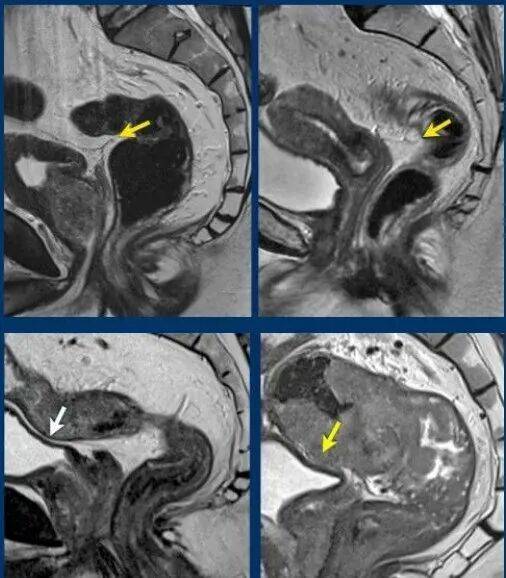

我们利用高分辨率的磁共振(MRI)等先进影像学检查,对肿瘤进行精确的 “TNM分期” 。这就像战前侦察,能清晰地判断肿瘤浸润的深度、范围以及与肛门括约肌的精确距离。这为制定科学、个体化的保肛手术方案提供了至关重要的依据。